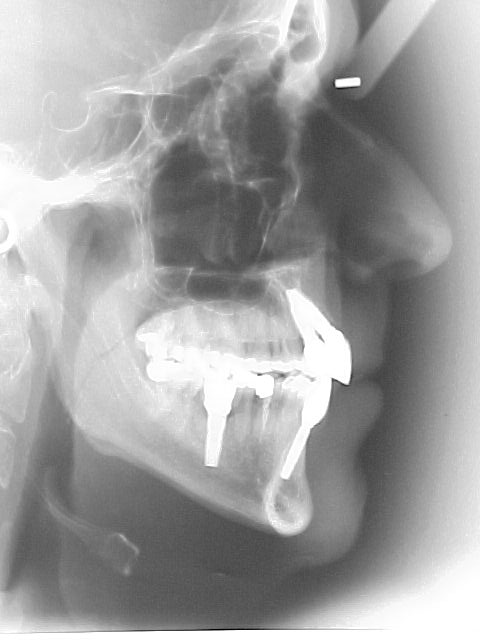

Preparação para instalação do "aparelho ortodôntico" (canino reconstruído em resina rápida autopolimerizável, retida por fio metálico sobre raiz residual)

Início do tratamento ortodôntico. Com a extrusão do canino estaremos induzindo ao nivelamento ósseo para a instalação de implante nesse local.